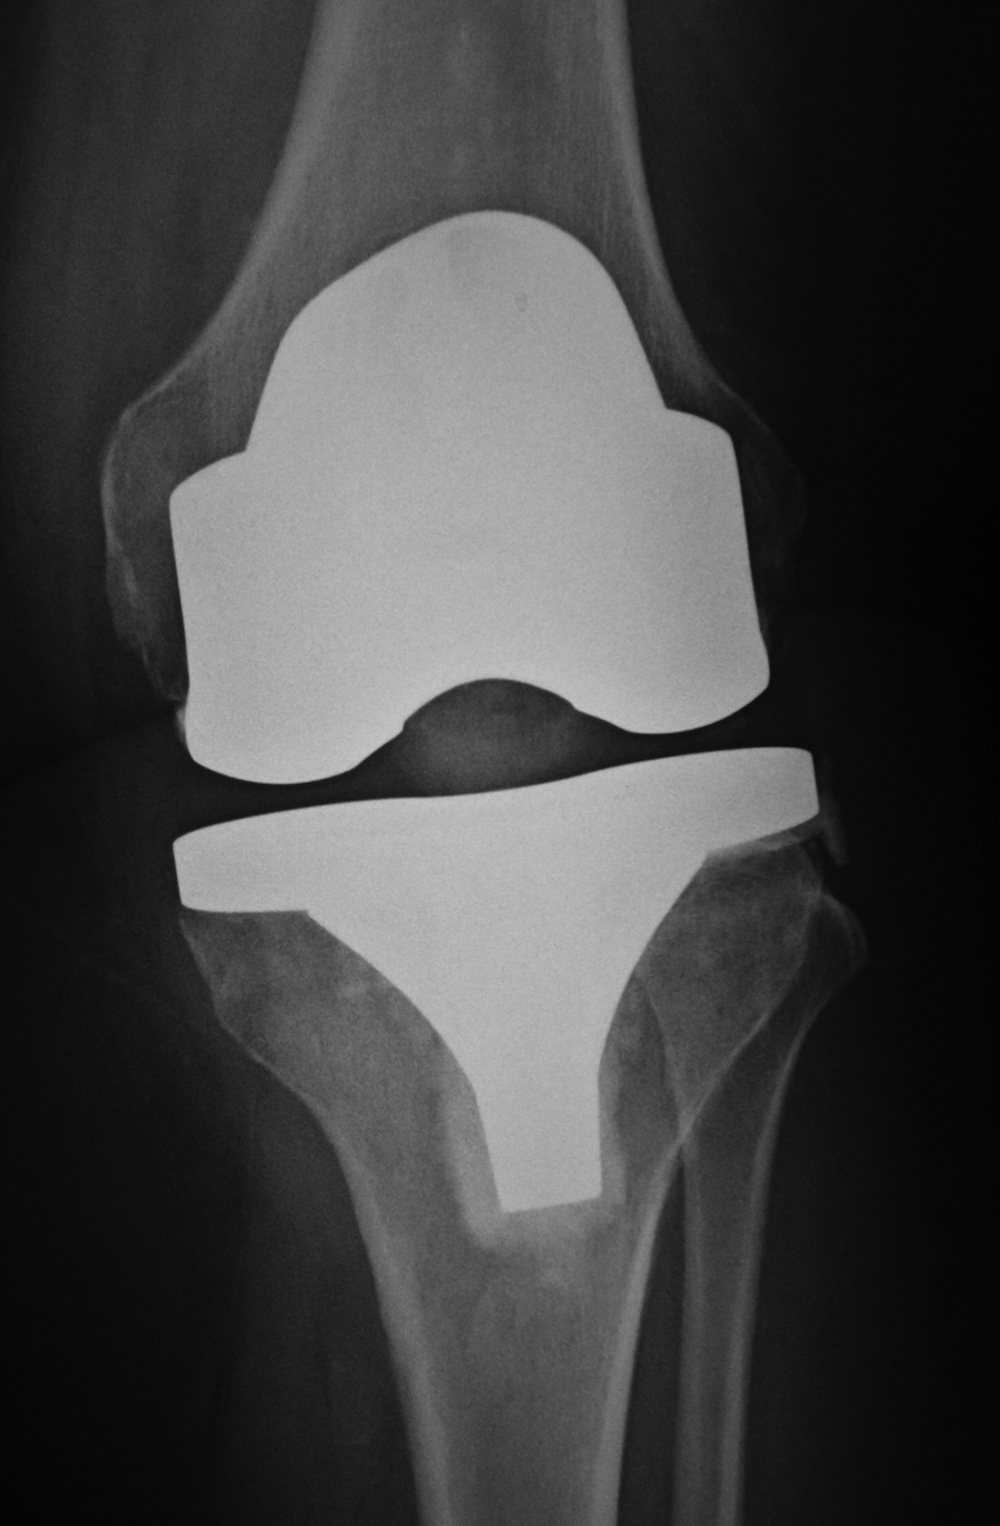

A posterior-stabilized knee or PCL-substituting knee has removal of the posterior cruciate ligament. This design limits posterior tibial translation in flexion. It contains a posterior cam, deeply dished articular surfaces, plus a third condyle or a central polyethylene post in the posterior middle portion of the tibial insert (figure: cruciate substituting TKA). In flexion this polyethylene post engages a transverse metal cam on the femoral component (Mulcahy, 2013). If the polyethylene post in the tibial insert does not have a metal backing it may not be visible on knee radiography. Usually one can differentiate cruciate-substituting from cruciate-retaining knee arthroplasty

on lateral views. The cruciate-substituting prosthesis often have a larger “box” or thicker femoral component.

Posterior cruciate substituting total knee prosthesis and patellar resurfacing. |

| 68 year-old woman treated for severe left knee osteoarthritis |

Note the large distal femoral box. There is a surgical drain in the suprapatellar space. |